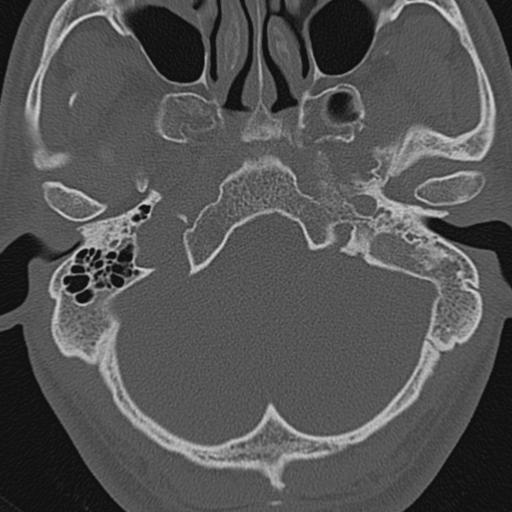

以下是引用zxl51642在2009-8-25 13:37:00的发言:[br]1、左侧慢性硬化型中耳乳突炎(中耳鼓室腔及听小骨受累),并胆脂瘤形成;2、左侧外耳道软组织密度影填塞,考虑炎性肉芽肿,建议结合临床;3、右侧颈静脉窝较左侧明显扩大,不排除颈静脉球瘤,建议mr进一步检查。

以下是引用随光逐影在2009-8-25 19:05:00的发言:[br]1)左侧慢性中耳乳突炎(肉芽肿或胆脂瘤形成),左侧外耳道炎性肉芽肿。2)右侧颈静脉球高位。